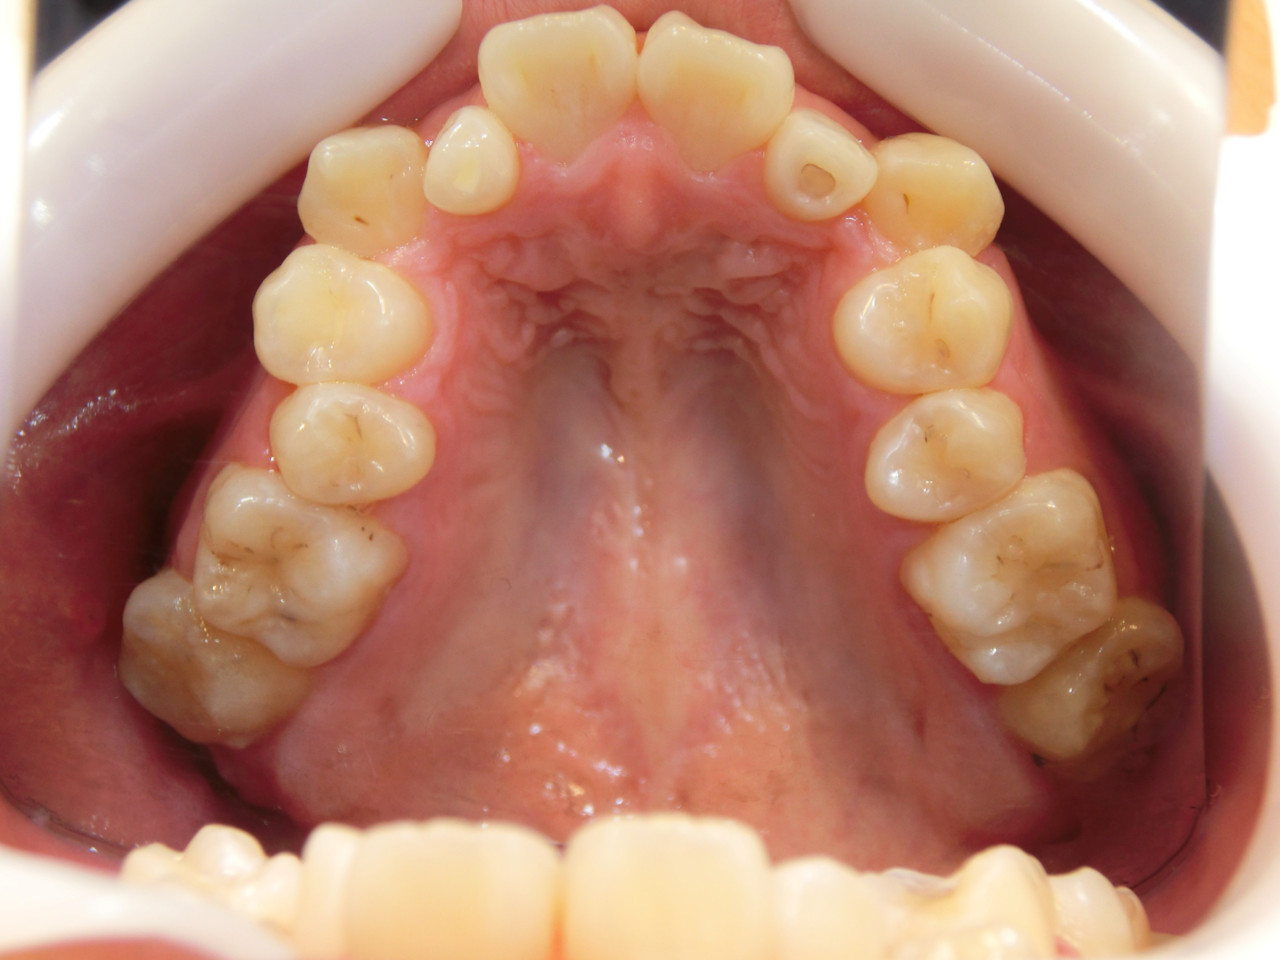

実例写真①

矯正前(上の歯)

矯正後(上の歯)

矯正前(下の歯)

矯正後(下の歯)

こちらの患者さまは、あごが小さいために前歯がきれいに並びきらず、「叢生(そうせい)」という前後がデコボコな歯並びでした。矯正後は、きれいに前歯が並んだだけではなく、上下の噛み合せも正しい位置に動き、しっかりと噛めるようになりました。

治療説明 歯科矯正でも目立ちにくい矯正方法です。透明に近いマウスピース型の矯正装置(アライナー)のため、歯に装着しても目立つことなく歯並びを矯正することが出来ます。また、一人ひとりの合わせて矯正装置を作製いたします。

治療期間 11か月

治療費用498000 円

治療の副作用(リスク)歯の動き方には個人差があり、予想された治療期間が延長する可能性があります。治療中は矯正歯科装置をつけるためハミガキを適切に行ってお口の中を常に清潔に保ち、さらに、かかりつけ歯科医に定期的に受診することが大切です。マウスピースの使用状況、定期的な通院など、矯正歯科治療には患者さんの協力が必要であり、それらが治療結果や治療期間に影響します。治療の経過によっては当初予定していた治療計画を変更する可能性があります。保定装置の装着時間が十分確保できない場合、歯並びや、咬み合せの「後戻り」が生じる可能性があります